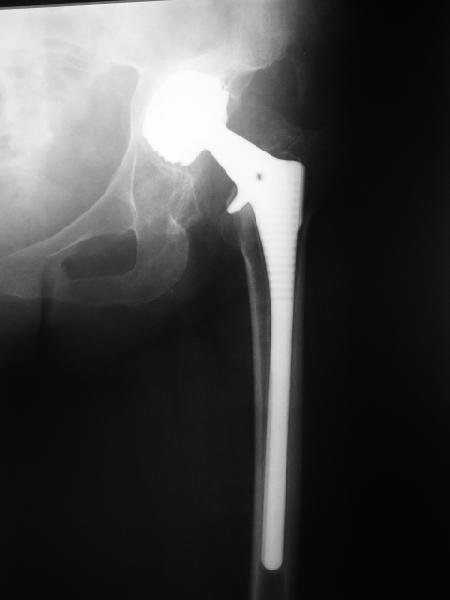

24 апреля 2005 г. правый сустав фас (тут и болит)

Простите-не заметил последнего приложения.Не вижу рентгенологических признаков loosening.Так что изотопы могли бы и помочь

На представленных Р-граммах явных признаков нестабильности эндопротеза нет. Чашка хоть и медиализирована, но стоит так же, как и 3 года назад и остеолиза нет. Есть остеолиз вокруг проксималного отдела ножки, но линия тонкая и не захватывает дистальный отдел. Судя по клинике, можно думать о травме (отрыв) ягодичных мышц в

2. Судя по рентгенограммам явной нестабильности тазового ибедренного компонентов не видно, но это не решает проблемы. Гематома? - пунктируйте - не инфекция ли? Посев пунктата нужен. 3. Не спешите - погодите по времени - возможно имеет место банальная травма в области искусственного сустава с гематомой - все пройдет. Ревизия только при убеждении в нестабильности компонентов сустава или при инфекции, что пока не манифестирует. Еще раз - не спешите, не горит. С уважением и с праздником. А Рыков Хабаровка.